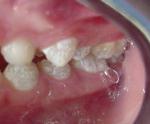

【虫歯の治療(左) / 歯周病のカラーテスト(右)】

軽度の虫歯治療は削らずに自然治癒を促すケースもあります。

中・重度のケースでも、必要最低限を削り大切な自然歯を残す治療を行ないます。

歯周病は、進行を止めるための内科または外科治療を行なうケースもあります。